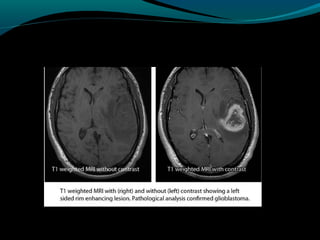

Glioblastoma

Maligno;

Origem astrocítica;

Grau IV;

60% dos astrocitomas;

15% das neoplasias intracranianas;

Mais frequente em adultos;

Sobrevida de 9 a 12 meses;

TC:

Geralmente supratentorial;

Infiltra substância branca;

Processo expansivo iso ou hipodenso de limites mal

definidos e necrose central;

Pode apresentar hemorragias;

Calcificações são raras;

RM:

Sinal heterogêneo em T1, T2 e FLAIR; (necrose, cistos,

hemorragia, neovascularização); mas predomina

hipointensidade em T1 e hiper em T2 e FLAIR;

Realce difuso e heterogêneo pelo Gd;